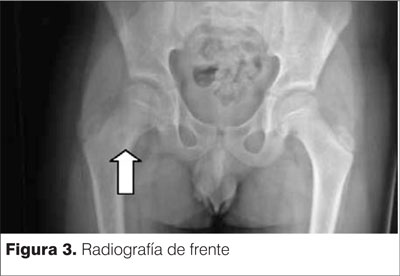

En la radiografía de cadera de frente se observa una imagen lítica redondeada con halo escleroso a nivel de cuello de fémur muy sugestivo de un osteoma osteoide. Imagen conocida como signo de la escarapela (figuras 3 y 4).